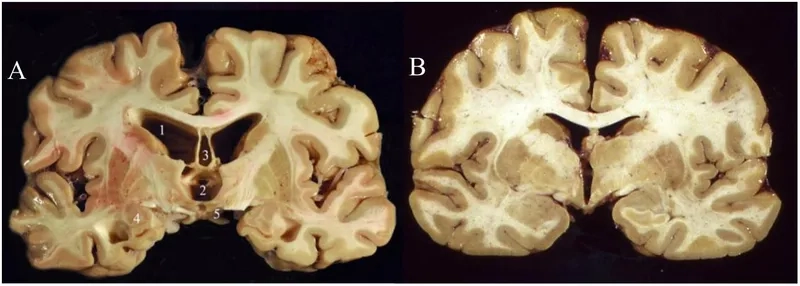

- The accumulation of an abnormal protein called tau forms clumps that slowly spread throughout the brain, killing brain cells and leading to progressive decline.

- As the disease progresses, cognitive impairment becomes more pronounced, with individuals experiencing significant memory loss, confusion, and impaired judgment, which can resemble Alzheimer's disease.

Visualizing concepts related to CTE